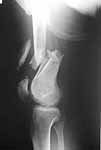

What would be your method of choice to fix this Gr IIIa open high energy supracondylar femur fx, neuro vasculary intact. 30YO male MBA hemodynamically stable, no chest injuries. Right temporal bone fx, no IC bleeding on the head CT. Images attached.

Date: 10/31/2004, 12:13 From Zsolt Balogh @ http://weborto.net/ Dear Alex, This is what we have done... As generally true for LISS look at the bone

not the hardware. There are two more screws above. The one not completely

in got damaged head. Zsolt